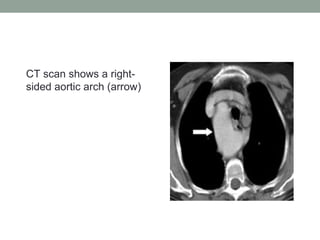

CT scan shows a right-

sided aortic arch (arrow)

CT scan showsa right- sided aortic arch (arrow)